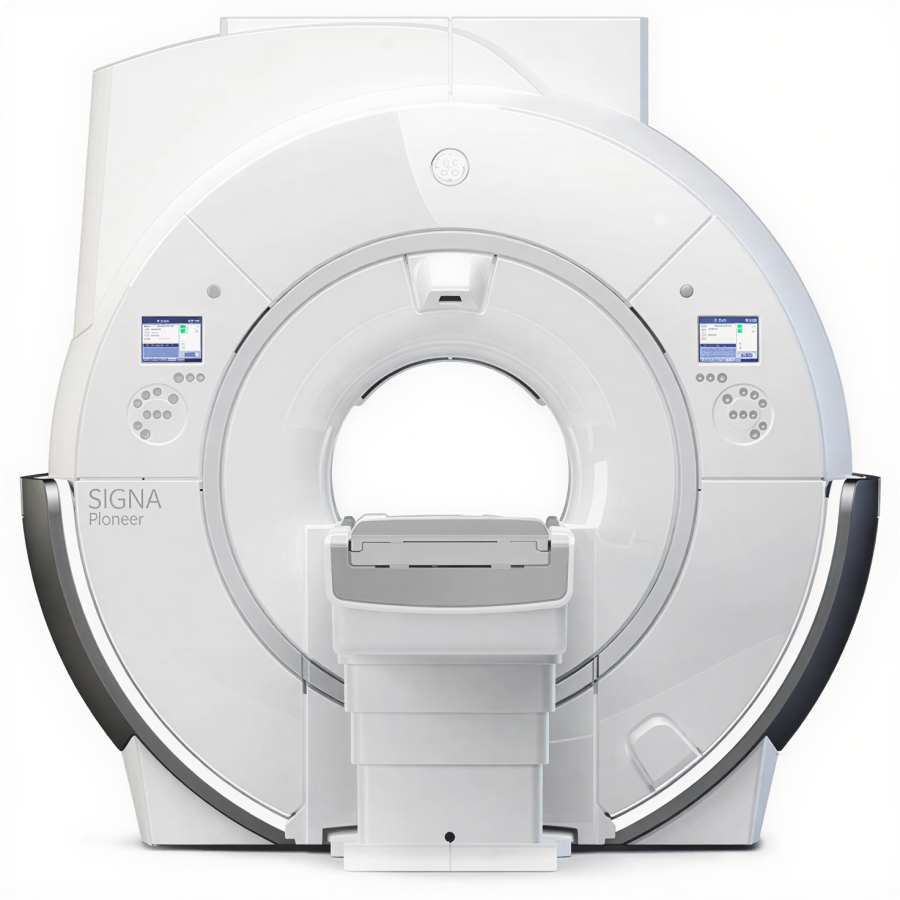

Магнитно-резонансный томограф GE SIGNA Pioneer 3 Тл — премиальная система для продвинутой МР-диагностики

GE SIGNA Pioneer относится к актуальному поколению 3T-систем семейства SIGNA, в которых сделан акцент на сочетании высокой однородности поля, развитой градиентной системы и цифровой архитектуры приёма сигнала. Платформа проектировалась как универсальное решение для нейрорадиологии, онкологии, кардиологии, ортопедии и целотельных исследований. Широкий тоннель и комфортный стол обеспечивают удобство позиционирования пациента и снижают долю прерванных исследований, а развитые средства коррекции движения и шумопонижения (включая технологии Silent и современные алгоритмы реконструкции) помогают получать стабильные диагностические изображения даже у сложных категорий пациентов.

Ключевым преимуществом GE SIGNA Pioneer является использование цифровой архитектуры Total Digital Imaging и современных градиентных модулей с высокой скоростью нарастания, что создаёт основу для продвинутых режимов диффузии, трактографии, функциональных и перфузионных исследований. Интеллектуальные технологии семейства SIGNA Works (нейро-, онко-, кардио- и body-пакеты), а также опции на базе методов глубинного обучения (AIR Recon DL и связанные решения) позволяют одновременно сокращать длительность протоколов и повышать информативность изображений. Интеграция c PACS/RIS по DICOM, поддержка удалённого сервисного мониторинга и возможность поэтапного расширения программного функционала делают систему удобным инструментом для центров, формирующих референсный уровень МР-диагностики и реализующих исследовательские программы.

| Тип магнита | Сверхпроводящий магнит с широким тоннелем |

| Диаметр тоннеля для пациента | 70 см |